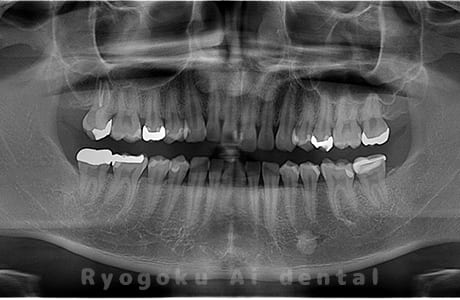

Case02

-

- 原因

- 下顎の水平埋伏智歯

- 治療内容

- 下顎の水平埋伏智歯を抜歯

<リスク・副作用>

手術後は痛み、腫れ、痺れなどの副作用が生じる場合があります。